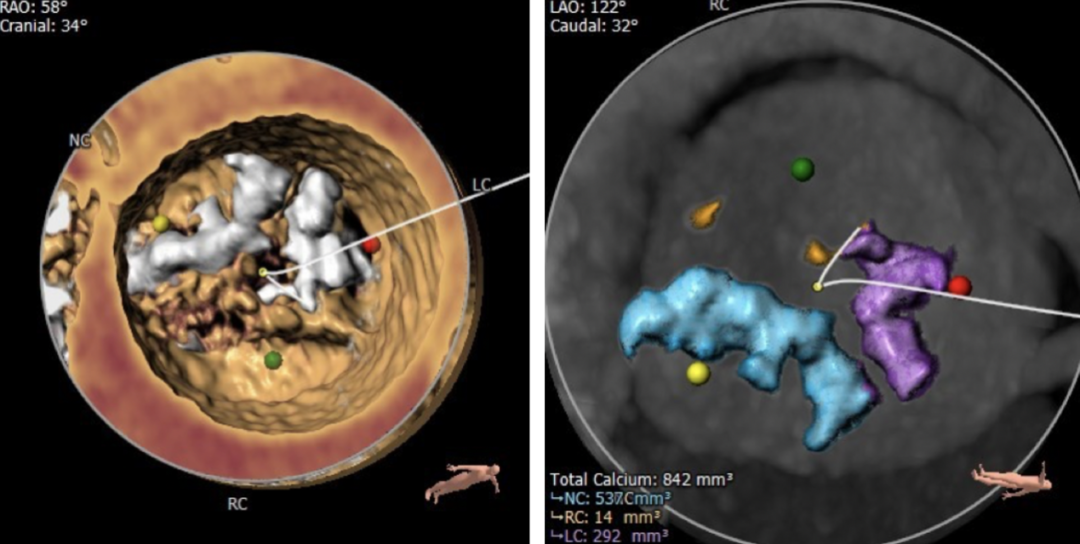

钙化分布

该患者左冠窦和无冠窦钙化严重,预估球囊扩张时推移左无的融合嵴难度较高,同时人工瓣膜释放时会偏向右冠窦,可能有显著变形并导致瓣周漏的风险。

冠脉风险方面,虽然左冠瓣瓣叶长度>冠脉开口距离,但是结合瓦氏窦内径,左冠窦瓣叶钙化分布等综合因素考虑,术中冠脉遮挡风险较小。